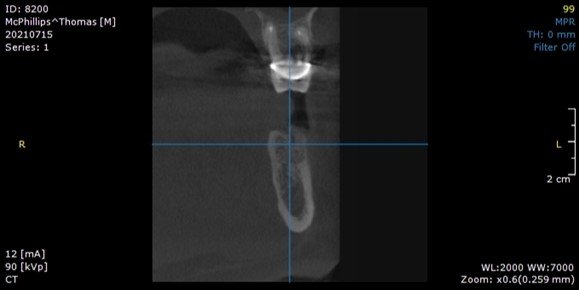

In the twelfth-month appointment, another CBCT was taken to evaluate the bone over implant #20. It can be seen on the CBCT image that there was a significant improvement in the thickness of the bone.